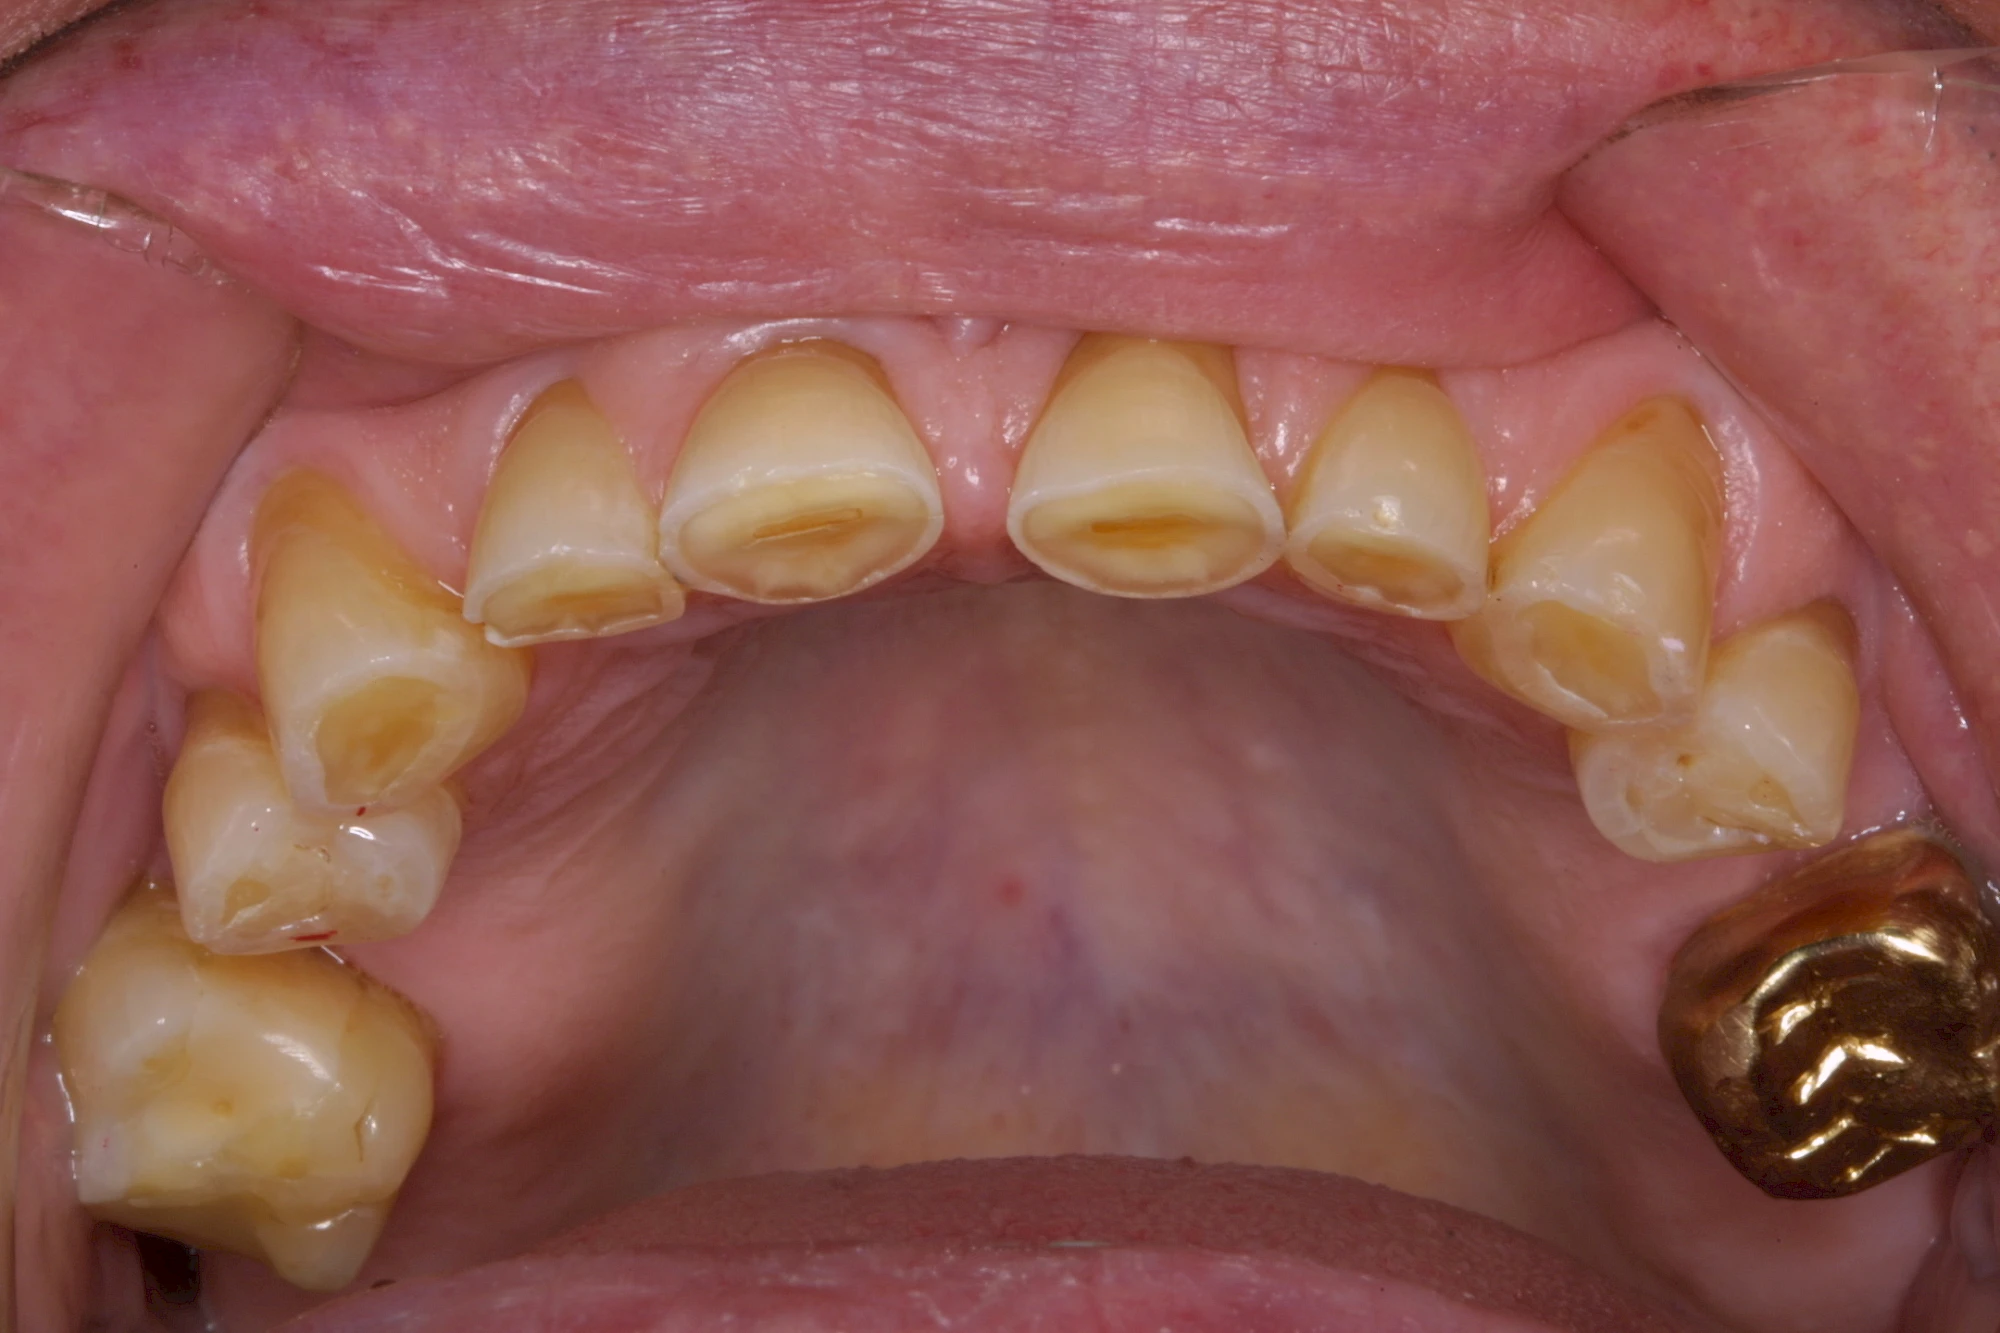

Auswaschung

Auswaschung (Erosion) dagegen ist eine Verschleißerscheinung der Zähne aufgrund von immer wiederkehrenden Säureangriffen durch die Nahrung, verstärkt zum Beispiel durch den Genuss säurehaltiger Getränke oder Speisen. Auch bei Menschen mit einer Essstörung (z. B. Bulimie) können die Zähne durch die Magensäure ausgewaschen erscheinen.